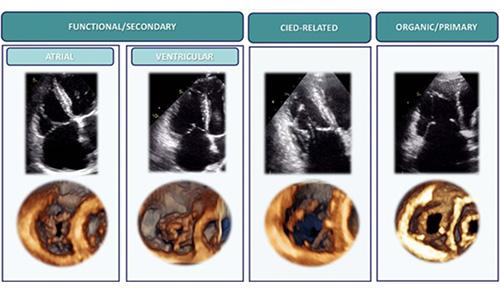

In 2025, cardiologists and cardiac surgeons at NewYork-Presbyterian led breakthroughs that impacted a range of diseases and conditions from advanced heart failure to pediatric valve disease. Physicians and researchers from Columbia and Weill Cornell Medicine pioneered the use of artificial intelligence to identify structural heart disease, launched a mobile app to expand access to heart failure education, performed one of the first split-root domino partial heart transplants, and more. Our experts remained at the forefront of innovative, multidisciplinary care, delivering comprehensive treatment for the most complex cardiac diseases.

Our world-renowned Columbia and Weill Cornell Medicine physicians and surgeons in our comprehensive cardiology, heart surgery, and vascular programs spearhead groundbreaking clinical and scientific research and provide the most innovative treatments to optimize patient outcomes for all stages of disease complexity. Our clinicians are experts in minimally invasive approaches and novel therapeutics for all types of heart disease and work across disciplines to provide compassionate care to all patients.